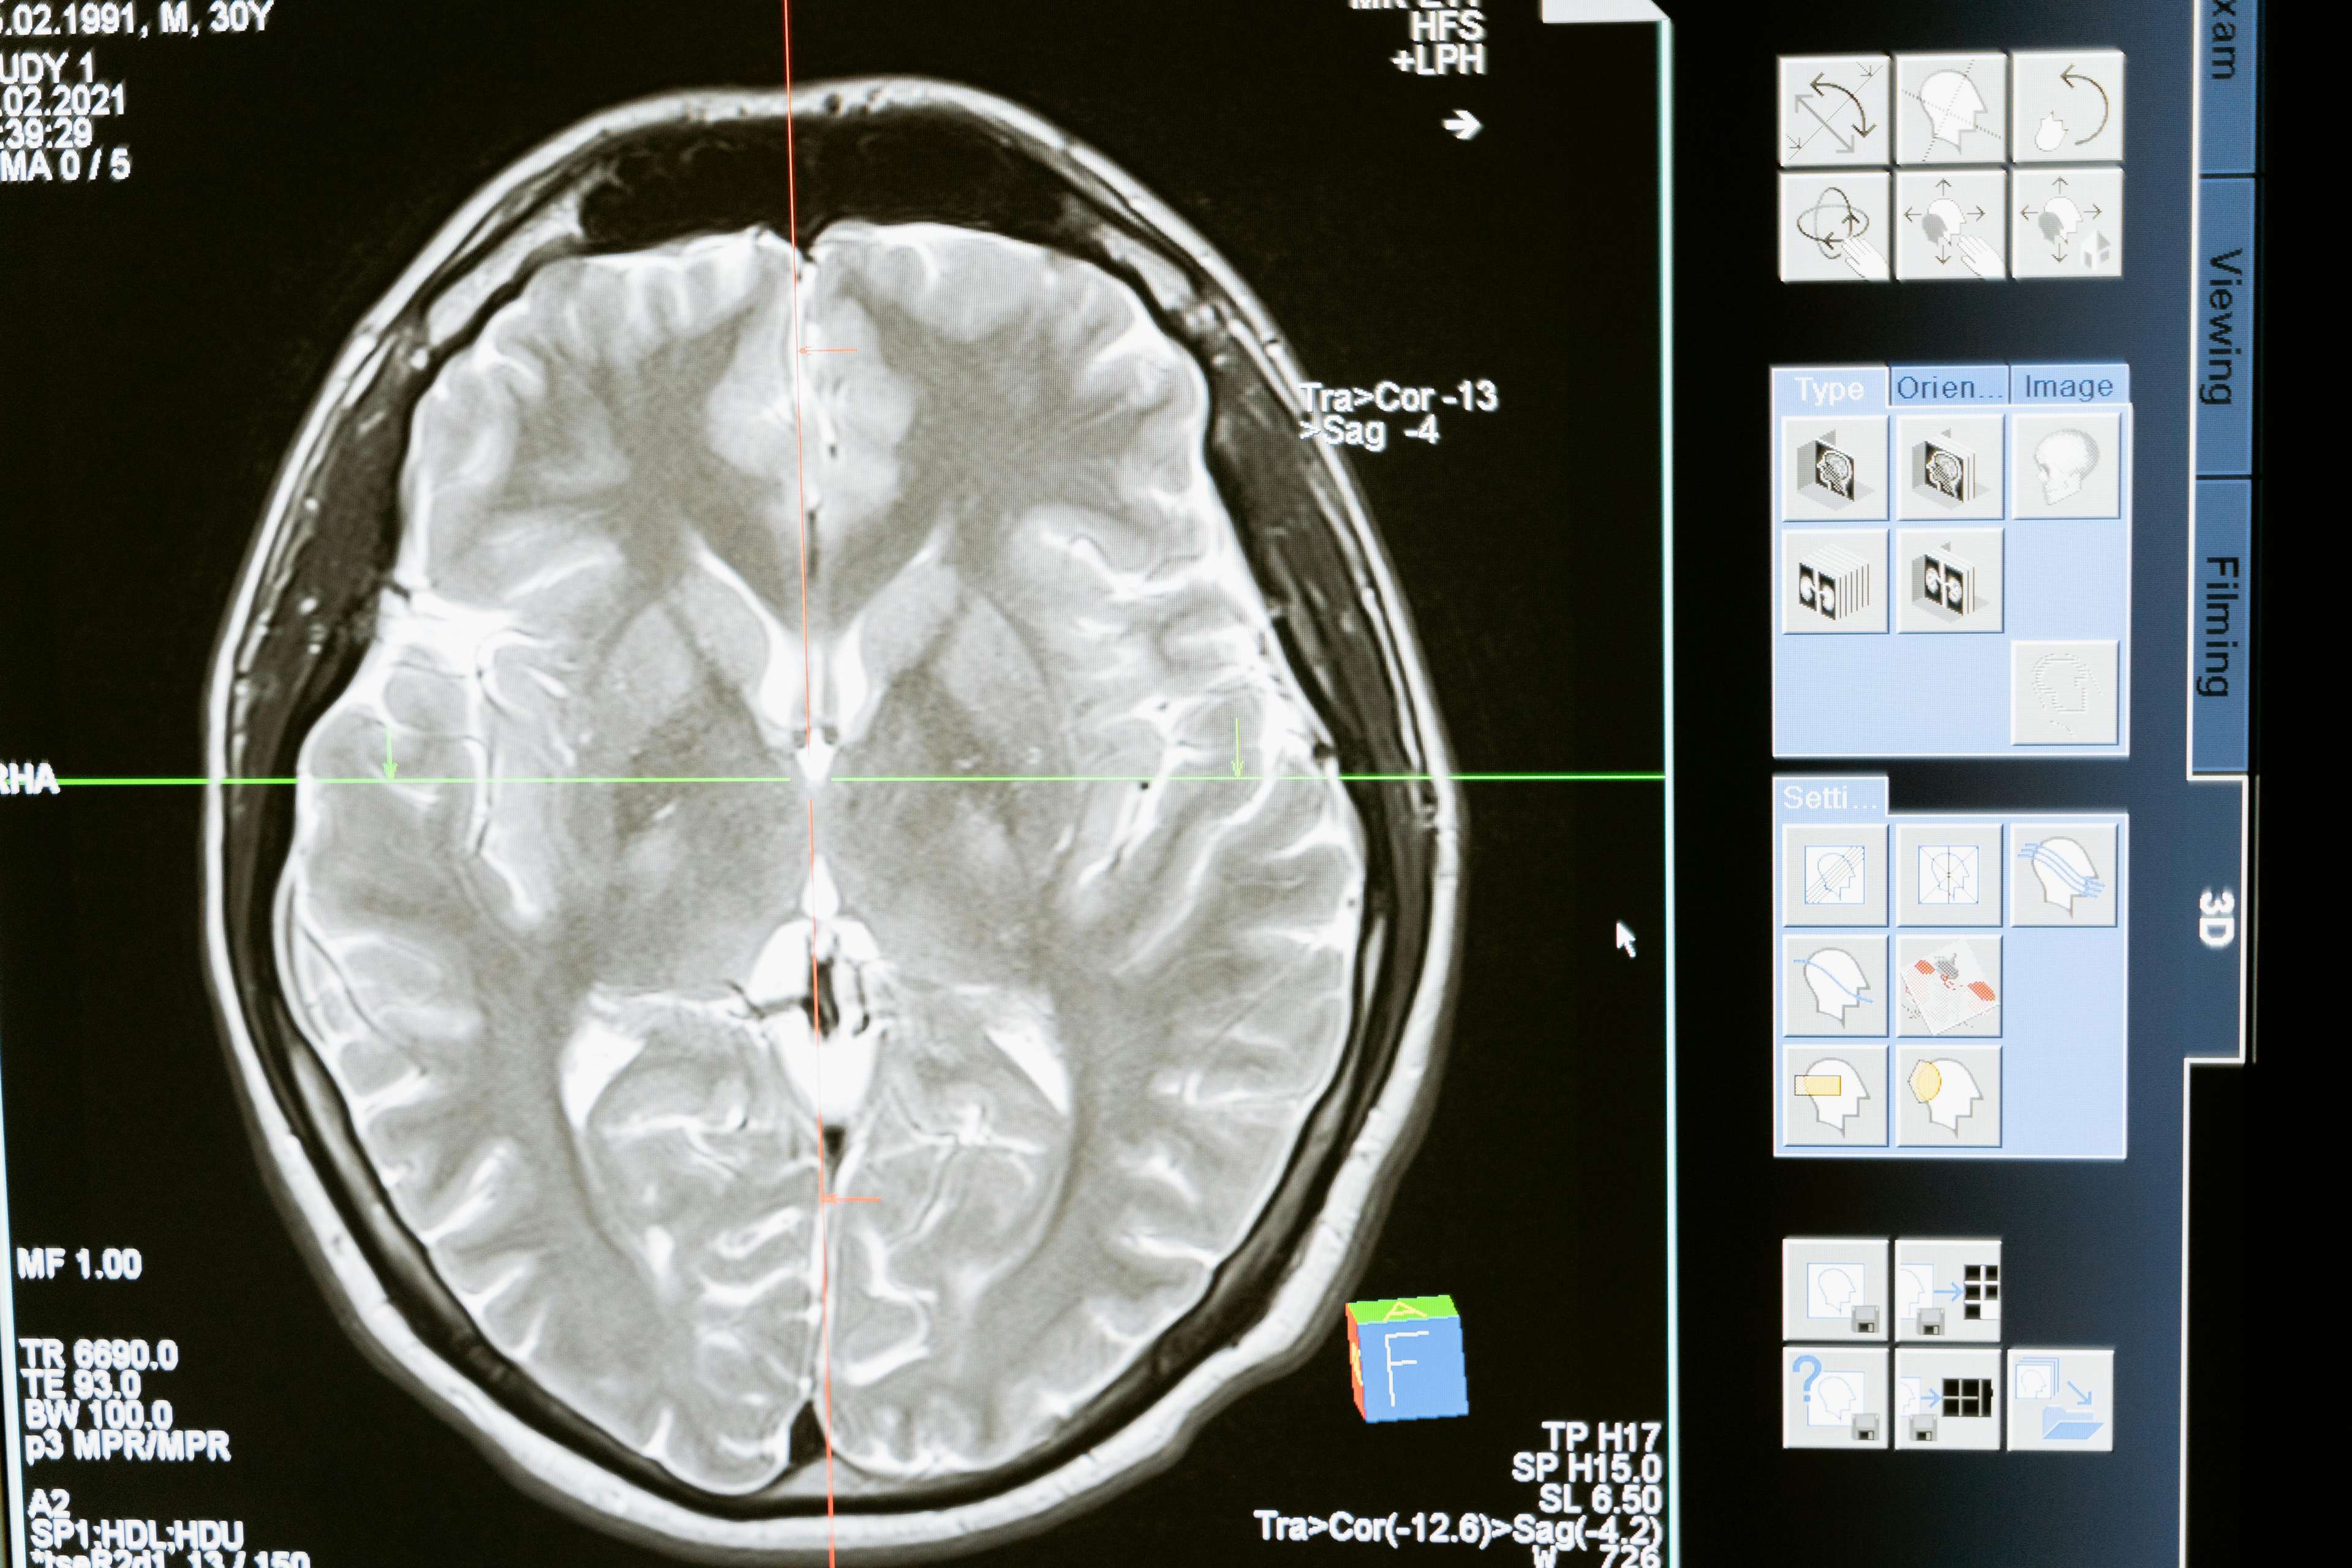

Ang malalim na pagpapasigla ng utak (DBS) ay isang pamamaraan ng kirurhiko na nagsasangkot ng pagtatanim ng isang aparato na nagpapadala ng mga impulses ng elektrikal sa mga tiyak na lugar ng utak. Ang teknolohiyang ito ay nasa loob ng maraming mga dekada, ngunit ang mga kamakailang mga pambihirang tagumpay ay naging mas epektibo, naa -access, at ligtas. Noong nakaraan, ang DBS ay pangunahing ginamit upang gamutin ang mga karamdaman sa paggalaw tulad ng Parkinson's, Dystonia, at Mahahalagang Paggamot. Gayunpaman, lumawak ang mga aplikasyon nito upang isama ang mga psychiatric na kondisyon tulad ng obsessive-compulsive disorder, major depression, at maging ang malalang sakit. Ang pamamaraan ay nagsasangkot ng pagtatanim ng isang elektrod sa utak, na konektado sa isang aparato na tulad ng pacemaker na bumubuo ng mga de-koryenteng impulses. Ang mga impulses na ito ay nag -regulate ng hindi normal na aktibidad ng utak, nagpapagaan ng mga sintomas at pagpapabuti ng kalidad ng buhay.